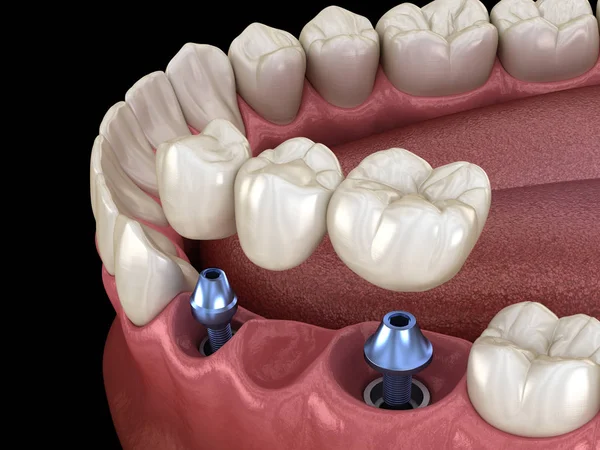

Carga inmediata.

Es la cirugía en la que se coloca el implante y la corona fija provisional, de inmediato o en menos de 48 horas.

Numerosos estudios han evaluado de manera positiva esta técnica, en cuanto a la integración con el hueso y la respuesta del implante frente a la intervención.

El éxito de la carga inmediata radica en muchos factores, tanto en la calidad de nuestro hueso, como en la elección de un implante y cuidado por parte del paciente.